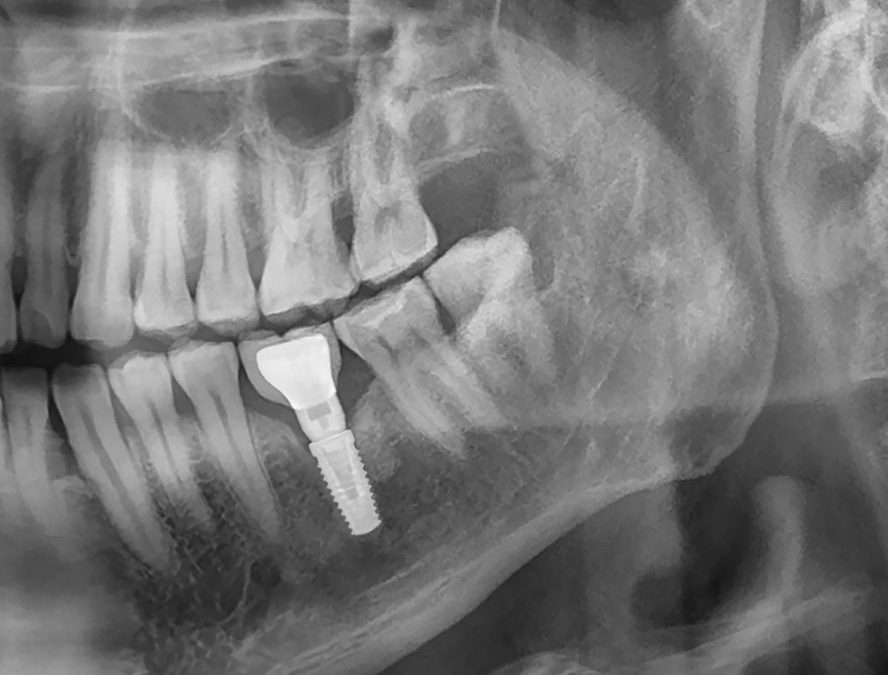

Les implants dentaires sont des racines artificielles en titane ou en zircone insérées dans l’os de la mâchoire. L’ostéointégration, processus par lequel l’implant fusionne avec l’os, est essentielle pour assurer la stabilité et la durabilité de l’implant. Si l’os est trop fin ou trop faible, l’implant peut échouer, ce qui peut entraîner une perte de l’implant et des complications supplémentaires.

Avant de procéder à l’implantation dentaire, il est essentiel de réaliser un bilan complet de votre santé osseuse. Cela inclut généralement des examens

radiographiques détaillés, comme la radiographie panoramique, pour évaluer la densité et la qualité de l’os.

Lors de cette évaluation, votre dentiste pourra déterminer si vous êtes un bon candidat pour un implant dentaire ou si des procédures supplémentaires, telles qu’une greffe osseuse, sont nécessaires.